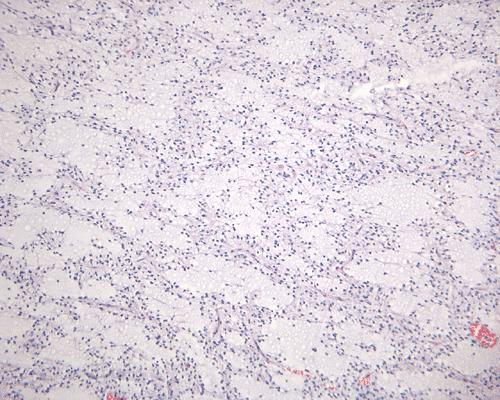

In a substantial amount of area, the tumor is composed of spindle cells with prominent perivascular arrangment and microcyst formation (Panel A and B). These vessels are surrounded by a thin rim of bipolar spindle cells (Panel C). The paucicellular perivascular mantle that is typical for ependymoma is absent in these perivascular arrangements. Adjacent to these perivascular arrangment is substantial amount of myxoid changes. On high-magnification, the tumor cells appear bland in histology, bioplar and spindle in shape, and admixed with a large amount of myxoid substance (Panel D and E). There is a lack of mitosis or significant pleomorphism. In some areas, the tumor is composed exclusively of spindle cells in a myxoid background with microcyst formation but without perivascular coronary arrangement of tumor cells (Panel F). It is not uncommon to observe areas with spindle cells clinging to the blood vessels (Panel G). In a minority of areas, there is increase in cellularity (Panel H). Some vessels seem to be composed of glomeruloids of blood vessels with plump endothelial cells (Panel I).

Histologically, the salient features of PMA are rather monotonous, small, spindle bipolar cells with angiocentric arrangement within a strikingly myxoid background. The myxoid basckground material is positive for Alcian blue but negative for PAS 1, 3,.  These features are well illustrated in our case. Occasional necrotic foci and mitotic figures can be present. Atypical mitotic figures and substantial nuclear pleomorphism should not be seen. Occasionally, the tumor cells infiltrate the surrounding non-neoplastic brain parenchyma but neither the histological feature nor radiological features would suggest a diffusely infiltrating astrocytoma. In contrast to pilocytic astrocytomas, PMAs do not possess a true alternating densely packed-loosely packed biphasic pattern, do not contain eosinophilic granular bodies or Rosenthal fibers 1, 4. Development of features that are seen in pilocytic astrocytomas such as the biphasic pattern and Rosenthal fibers have been described by Fernandez et al 4. These features are uncommon at the initial presentation but they can develop after chemotherapy. Although these features may suggest maturation of the tumor after chemotherapy, no association with improved prognosis has been described in the study by Fernandez et al 4. The angiocentric arrangement of tumor cells is another trap as it would suggest ependymoma. However, these arrangements are more irregular and fibrillar than the perivascular rosettes in ependymomas.